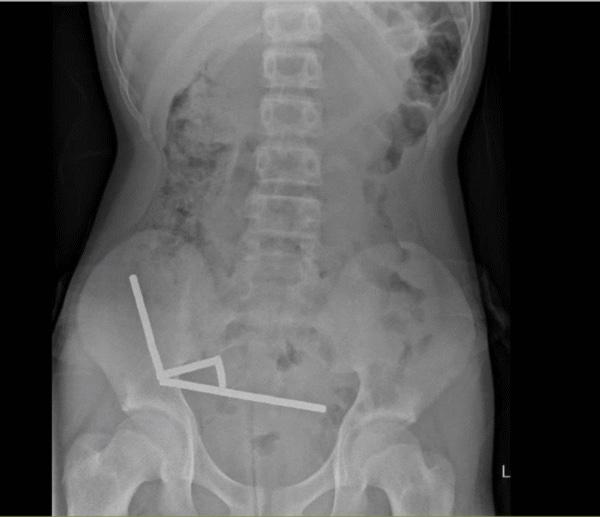

Die Magnete haben sich im Darmtrakt verbunden.

Der Teenager wurde mit Bauchschmerzen ins Spital eingeliefert und gestand dort, eine Woche zuvor etwa 80 bis 100 Magnete verschluckt zu haben. Durch ein Röntgen fanden die Ärzte heraus, dass sich die Magnete in seinem Verdauungstrakt zu 4 stabförmigen Gebilden verbunden zu haben.

Die Magnete mussten operativ entfernt werden, da sie Teile des Dünndarms und Blinddarms zusammendrückten und zu Gewebeschäden wegen Blutmangels, sogenannten Drucknekrosen, führten. Während der Operation sahen die Ärzte jedoch, dass es sich um fast 200 Magnete handelte. Wieso das Kind so viele Magnete verschluckt hatte, ist nicht bekannt.